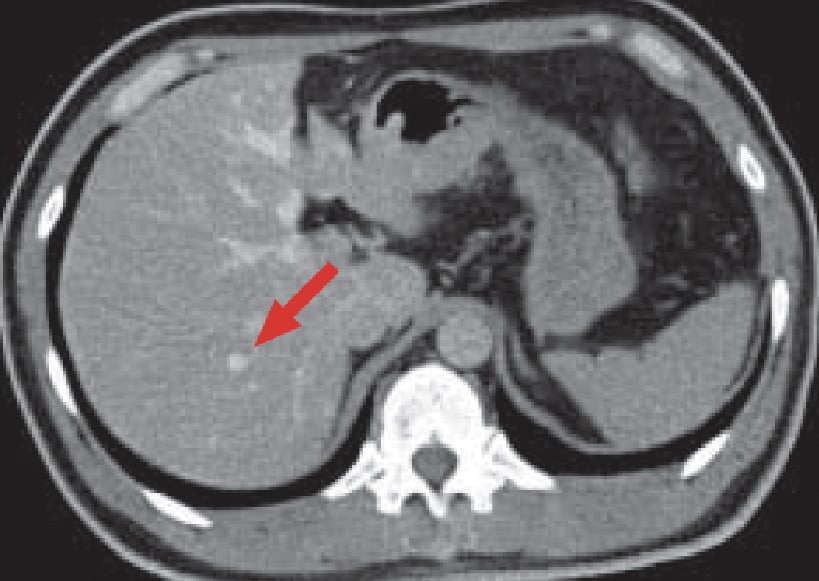

Hepatic arteriography (a) showed relatively dark tumor-staining (red arrow) in S8 of the liver.

CTAP (b) showed portal blood flow to be deficient, Phase 1 (c) of CTHA showed intense dark staining throughout the liver, and Phase 2 (d) showed corona-like wash-out, so the lesion was judged to be typical hepatocellular carcinoma (HCC).